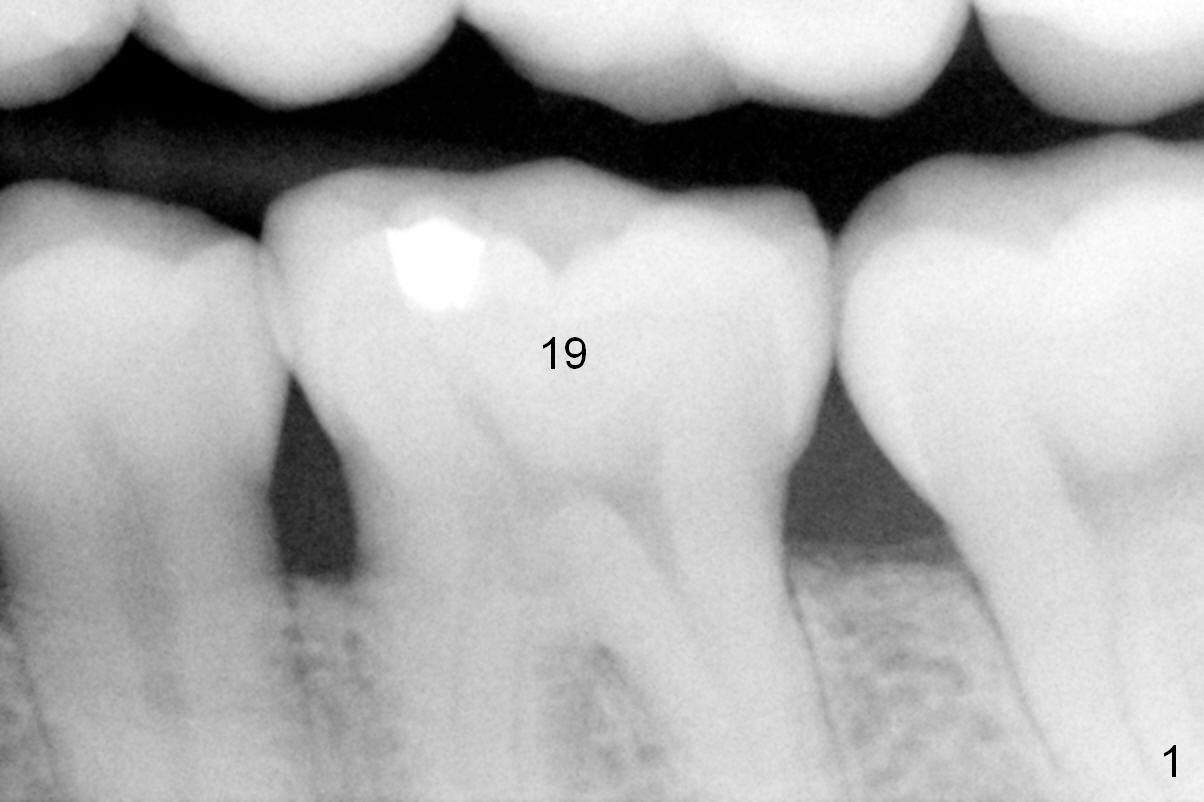

The mesial and distal crests of the tooth #19 were even for a 50-year-old man 7 years ago. Three years later, swelling developed around the distal root with bone loss (Fig.2 *). Three months later, localized swelling occurred (Fig.3 *) with oozing. The patient had thrombopenia (platelet 40 K). The tooth was extracted with suture. There is distolingual root tip resorption. Two months and a half later (Fig.4), a 6x17 mm implant was placed (Fig.5). The implant osteointegrated 5 months postop (Fig.6). The distal crest re-appears 5 months (Fig.7), 2 years (Fig.8) and 2 years 8 months (Fig.10) post cementation. At the last appointment, the patient complained of pain and swelling at #30 with mesial bone loss (Fig.10 *), as compared to Fig.9 taken 9 years ago. The mesiolingual pocket is deep. After scaling and Chlorhexidine irrigation, Arestin is locally administered.